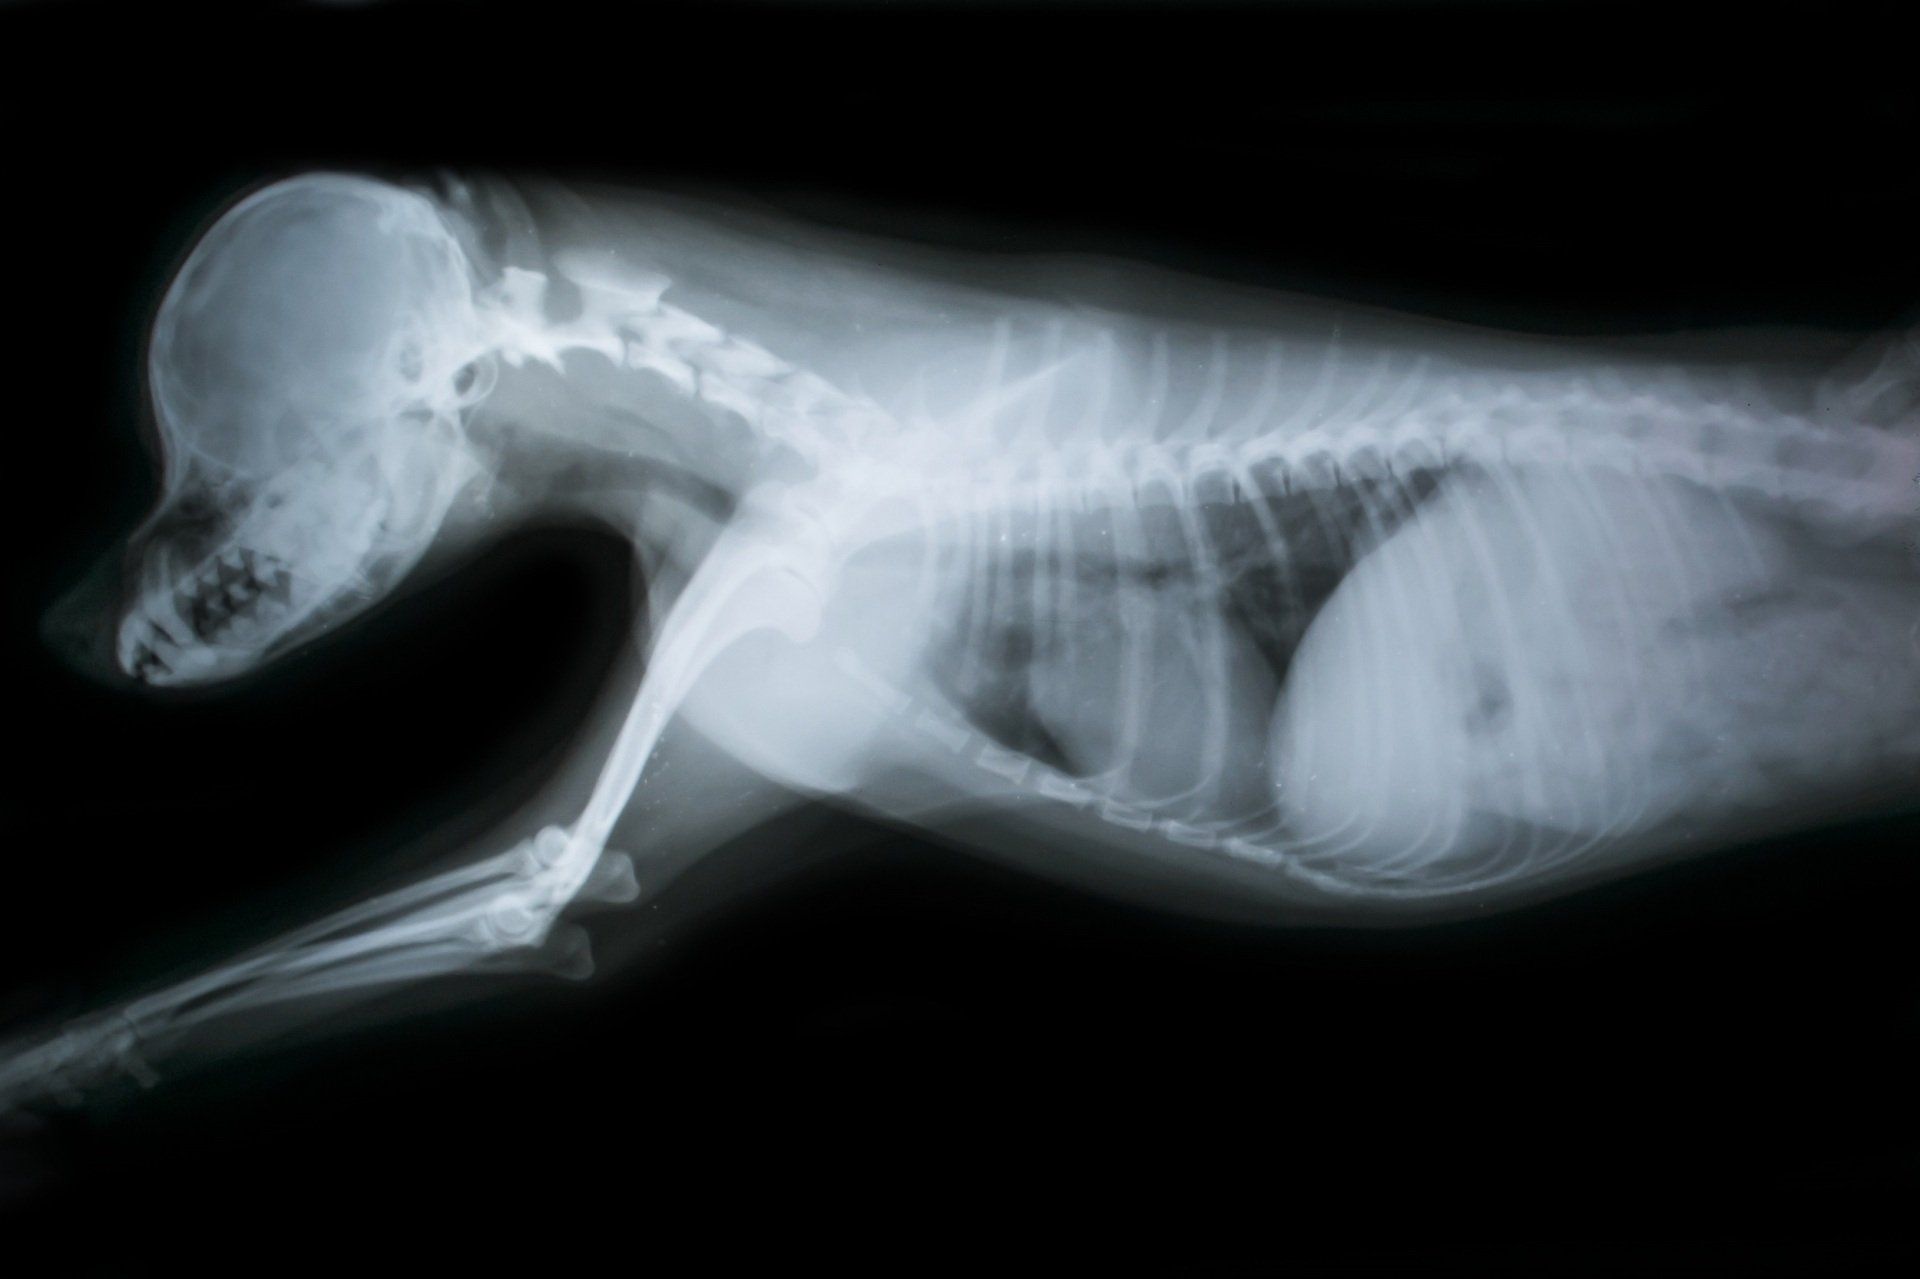

Radiologia clinica veterinaria

La radiografia è uno strumento importante che può aiutarci a fare una diagnosi corretta.

Una radiografia è un “tipo di fotografia” che può guardare all'interno del corpo e rivelare immagini che non possono essere, in alcun modo, rilevabili dall'esterno. La radiografia può essere utilizzata per valutare quasi ogni organo del corpo. Gli studi radiografici sono indispensabili nel primo approccio, soprattutto per le patologie dell’apparato locomotore.

La nostra clinica dispone di un apparecchio radiologico di ultima generazione ad alta frequenza con acquisizione digitale delle immagini radiografiche di alta definizione, che permette al medico di acquisire delle immagini in breve tempo. Grazie all'alta risoluzione delle radiografie, possiamo facilmente vedere organi in tutti gli animali, da uno più piccolo a uno grande. Possiamo valutare le diverse condizioni di salute, come ad esempio le masse tumorali, corpi estranei, le fratture delle ossa, patologie articolari, gravidanza e tutto quello che può essere rilevato con alta precisione e definizione dell'immagine.

Previa sedazione dell'animale, si possono realizzare radiografie dentali che permettono al medico di valutare la salute delle radici dei denti e identificare una serie di problemi che non sono visibili alla visita odontostomatologica tra cui: tumori, inclusioni dei denti, fratture, ascesso della radice del dente